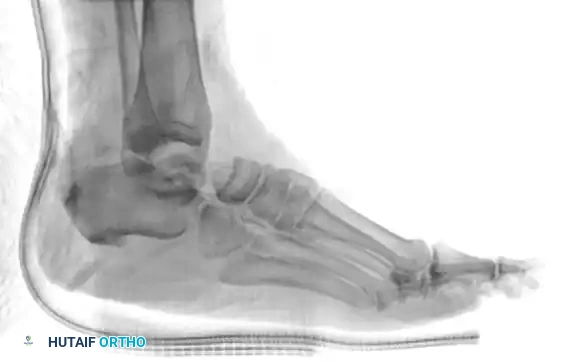

Standard trauma radiographs of the ankle (AP, lateral, and mortise) and foot (AP, lateral, and oblique) are required.

Radiographic appearance of a medial subtalar dislocation. The talonavicular and talocalcaneal joints are completely disrupted.

Radiographs demonstrating a lateral subtalar dislocation before and after reduction.